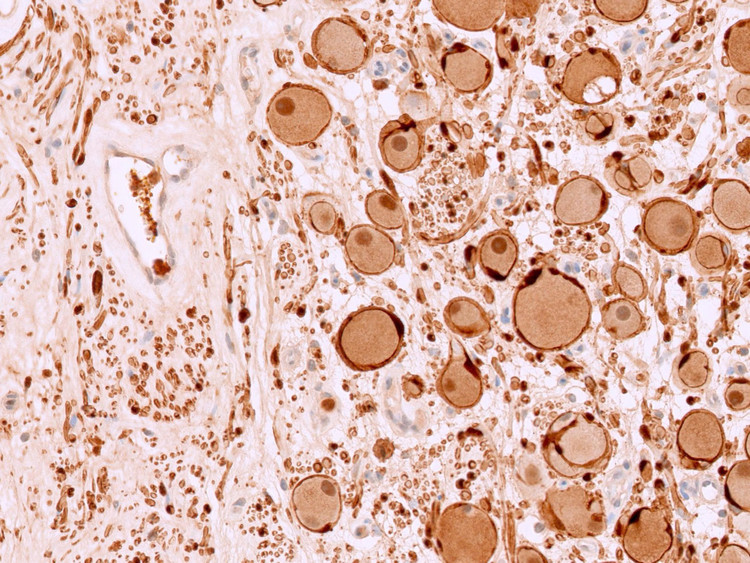

Kết quả xét nghiệm là u nguyên bào thần kinh đệm típ đang biệt hóa (Ganglioneuroblastoma). Đây là một loại u thần kinh hiếm gặp, nếu không được phát hiện sớm có thể dẫn đến di căn, khó điều trị và giảm cơ hội sống của người bệnh.

Biểu hiện tế bào của u nguyên bào thần kinh Ganglioneuroblastoma - Ảnh BVCC